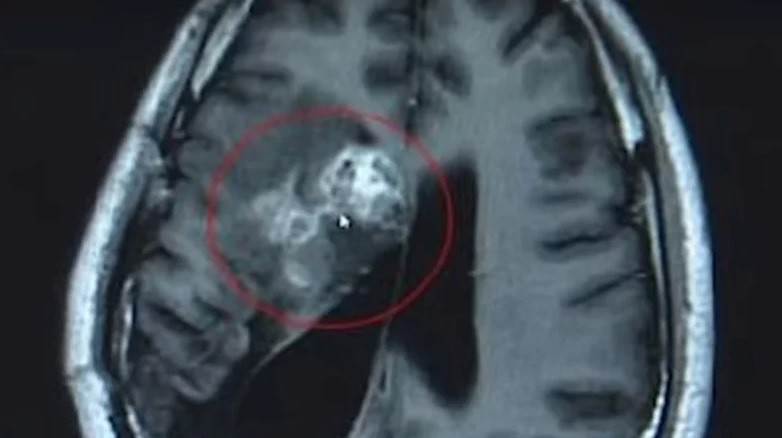

Un hombre fue operado a finales del pasado mes en un centro médico de la provincia de Guangdong, China, donde le extirparon de su cerebro un parásito vivo de doce centímetros de largo. El gusano se alimentó de sus tejidos durante quince años. Aparentemente, todo se inició por comer caracoles que no estaban bien cocidos.

Según publicó Russia Today, el neurocirujano Gu Youming, quien dirigió la operación que duró más de dos horas, explicó que si no extraían el parásito, la tenia habría seguido comiendo la masa cerebral del hombre, lo que podría haber producido parálisis o la muerte.